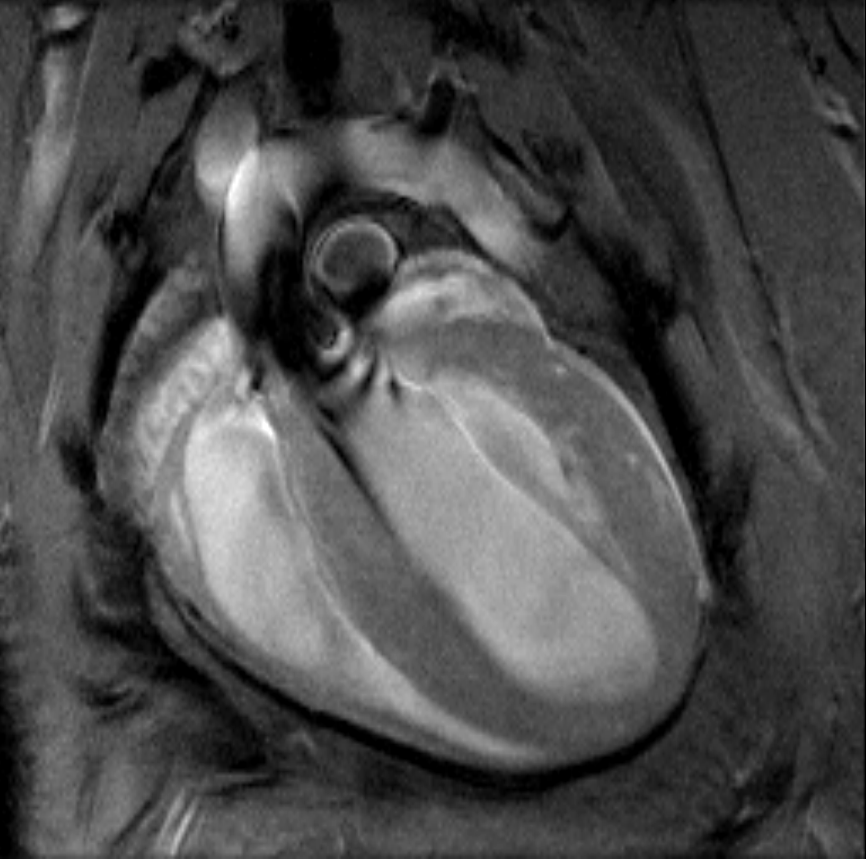

• MRI sequence portfolio of more than 1,000 sequence variations, including wireless cardiac imaging using navigator based IntraGate methods with cartesian or radial readout, as well as short echo time imaging, such as UTE and ZTE